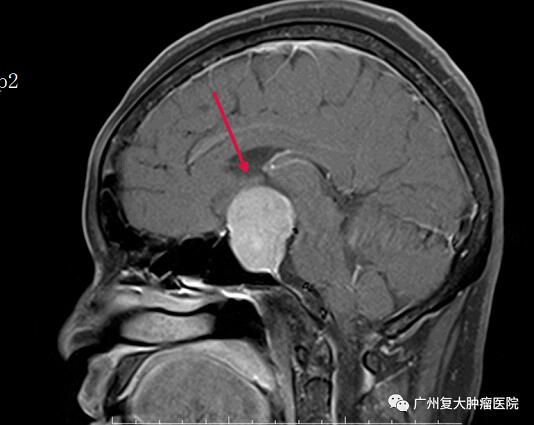

术前

专家表示,垂体瘤是指颅咽管上皮细胞、垂体前、后叶出现的肿瘤病变,发病率约占颅内肿瘤患者的10%,以女性居多。垂体瘤常见的生长方式是向鞍上发展,压迫视交叉神经和视神经,从而引起视力下降和视野缺损,需要尽快手术,解除对视神经的压迫,恢复视力。